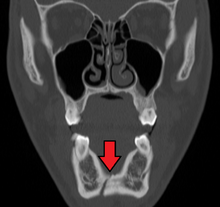

Mandibular fractures are typically the result of trauma. This can include a fall onto the chin or a hit from the side.[1] Rarely they may be due to osteonecrosis or tumors in the bone.[2] The most common area of fracture is at the condyle (36%), body (21%), angle (20%) and symphysis (14%). While a diagnosis can occasionally be made with plain X-ray, modern CT scans are more accurate.[1]

Computed tomography is the most sensitive and specific of the imaging techniques. The facial bones can be visualized as slices through the skeletal in either the axial, coronal or sagittal planes. Images can be reconstructed into a 3-dimensional view, to give a better sense of the displacement of various fragments. 3D reconstruction, however, can mask smaller fractures owing to volume averaging, scatter artifact and surrounding structures simply blocking the view of underlying areas.